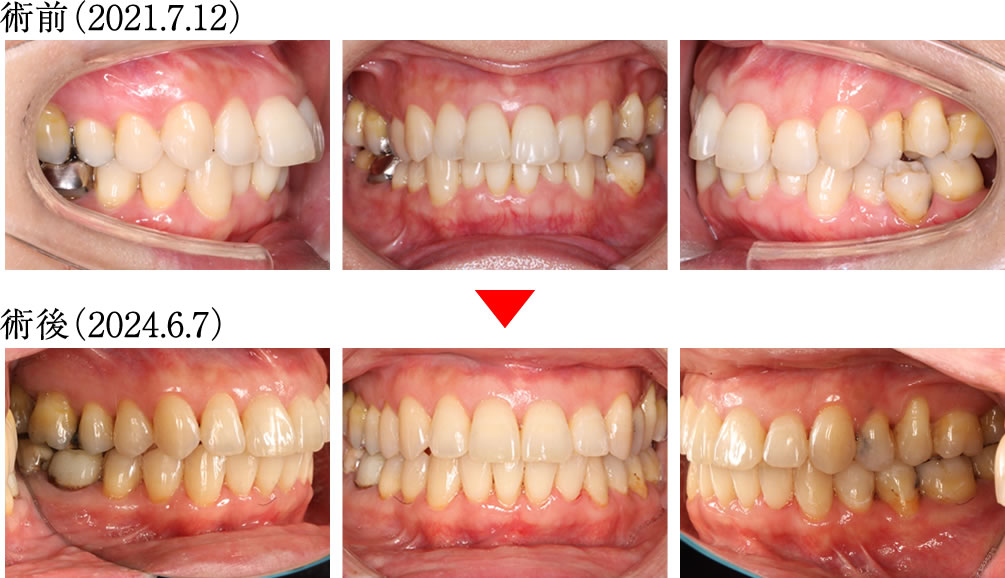

術前は前歯の噛み込みが深く、奥歯も正しく噛み合わない不安定な歯並びでしたが、術後は前歯から奥歯までバランスよく整い、理想的で美しい歯並びへと改善されました。